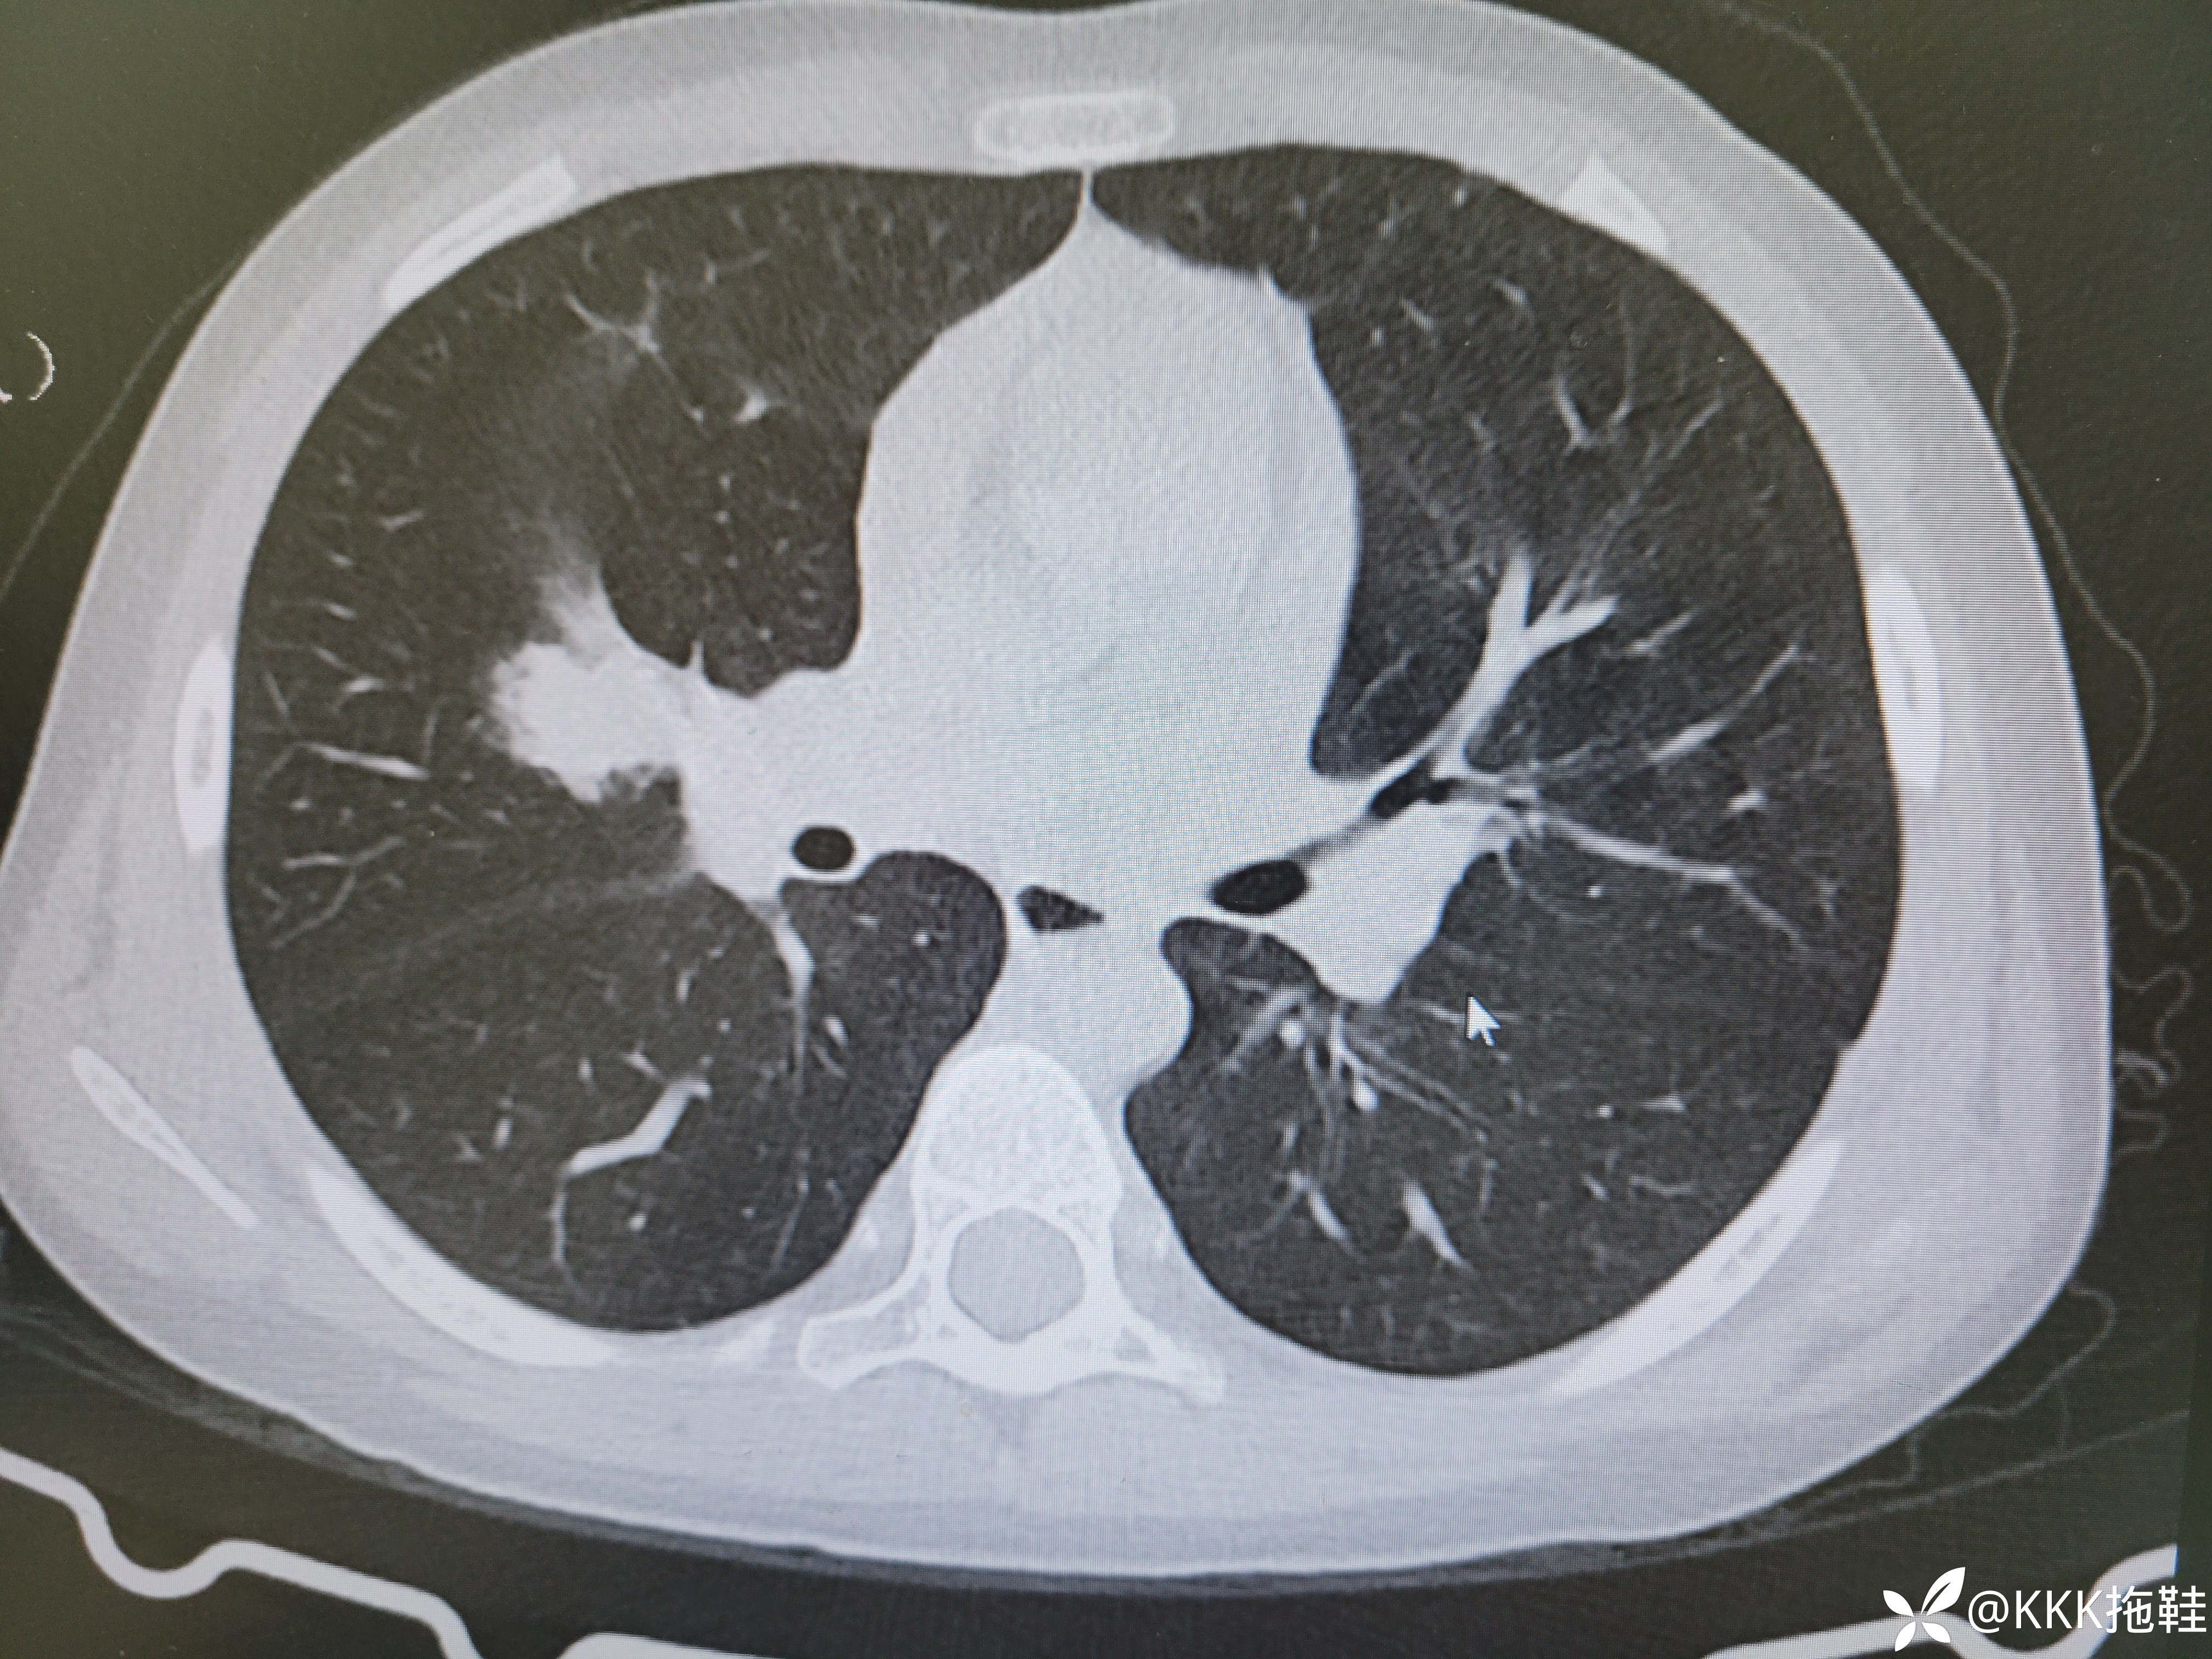

入院当天CT